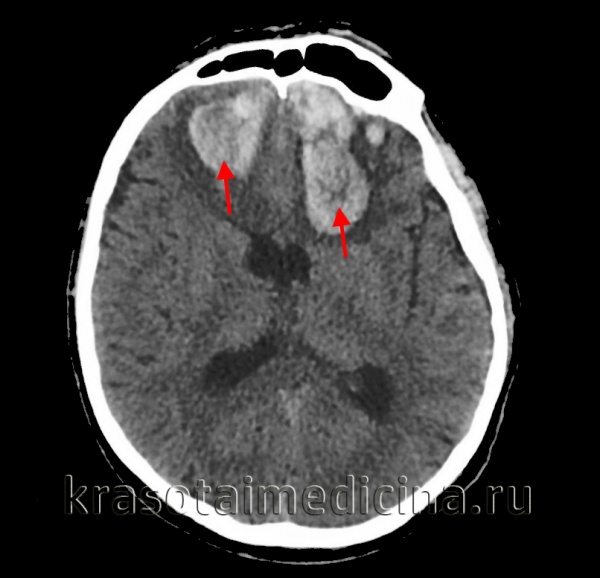

- КТ головного мозга. Как правило, на томограммах внутримозговая гематома имеет вид очага гомогенной плотности округлой или овальной формы. Если гематома сформировалась в результате ушиба головного мозга, то она обычно имеет неровный контур. С течением времени происходит уменьшение плотности гематомы до изоплотного состояния, при котором ее плотность соответствует плотности мозговой ткани. Для малых гематом этот период составляет 2-3 недели, а для средних — до 5 недель.

Внутримозговая гематома — ограниченное скопление крови в веществе головного мозга, оказывающее сдавливающее, смещающее и повреждающее воздействие на расположенную вблизи мозговую ткань. Внутримозговая гематома клинически характеризуется общемозговыми и очаговыми симптомами, которые зависят от места расположения гематомы и ее объема. Наиболее достоверно внутримозговая гематома диагностируется сочетанным применением КТ и МРТ головного мозга, а также ангиографического исследования сосудов мозга. Небольшая внутримозговая гематома может быть пролечена консервативно, большая внутримозговая гематома — только хирургически, путем удаления или аспирации.